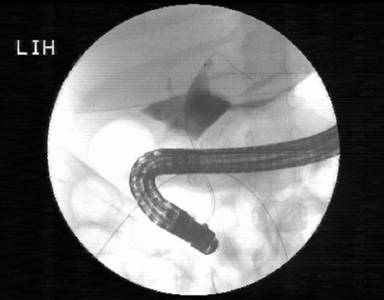

A 4-year-old girl who was otherwise well, presented at the emergency ward of a different centre in our city having had acute abdominal pain associated with obstipation for 3 days. She was found to be very ill, anicteric and dehydrated. She was rehydrated with fluids. Investigation revealed that her liver function was normal; however, her serum amylase level was 906 IU/L (reference range: 25-125 IU/L), and her lipase level was 451 IU/L (reference range: 22-51 IU/L); her total leucocyte count was 12,700 µL-1 (reference range: 4,000-10,000 µL-1) with predominant neutrophilia. Her CRP was 102 mg/dL (reference range: 0-6 mg/dL) and serum calcium was 7.5 mg/dL (reference range: 8.4-10.2 mg/dL). MRCP showed a bulky pancreas and a normal, non-dilated biliary system (Figure 1). She was managed therapeutically as a case of acute pancreatitis. However, she continued to have pain and developed fever and distension of the abdomen from the 4th day of her admission. She was found to be very toxic. Her leucocyte count rose to 24,900 µL-1 with 96% neutrophilia. Amylase and lipase on day 4 increased additionally to 1,300 IU/L and 2,957 IU/L, respectively. Abdominal ultrasonography showed massive ascites and an ascitic fluid examination showed it to contain bile with bile salts and bilirubin. Laparoscopic drainage of the ascitic fluid was carried out with a thorough peritoneal lavage with warm normal saline and a peritoneal drain was inserted. Abdominal distension decreased but, even on 10th postoperative day, she continued to have a large amount of bilious ascitic fluid draining from the peritoneal drain. Fever persisted in spite of receiving broad spectrum antibiotics. She was referred to our centre for further management. We performed an ERCP under anesthesia (Olympus TJF160 endoscope, Singapore, Singapore) which showed evidence of a bile leak from the middle part of the common bile duct, although the duct was not well delineated (Figure 2). The intrahepatic radicles were, however, not dilated. An endoscopic sphincterotomy was carried out and a biliary stent (7 Fr in diameter, 9 cm in length) was placed across the leak site into the left intrahepatic duct.

Figure 2. Initial ERCP showing a leaking bile duct, biliary sphincterotomy and stenting. |